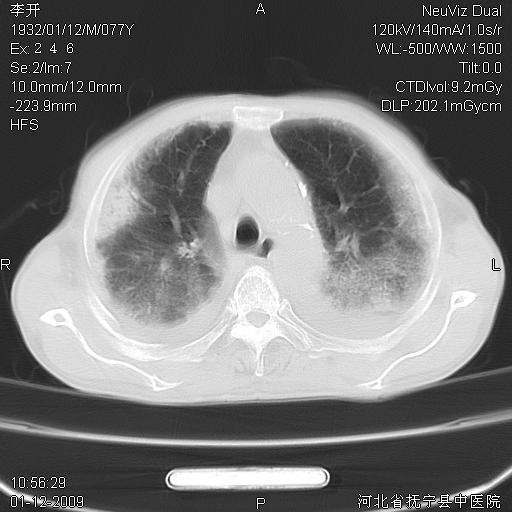

以下是引用黑白光影在2009-1-19 16:49:00的发言:[br]心衰肺水肿;心包、胸腔积液;冠脉钙化;肺部感染。